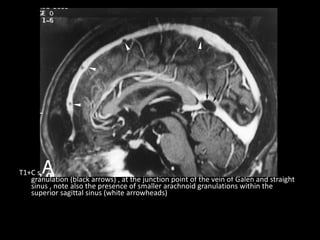

T1+C shows a large CSF-isointense filling defect , consistent with an arachnoid

granulation (black arrows) , at the junction point of the vein of Galen and straight

sinus , note also the presence of smaller arachnoid granulations within the

superior sagittal sinus (white arrowheads)